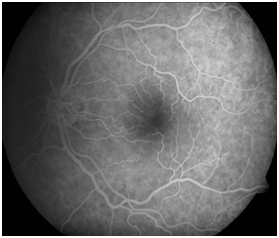

The primary pathology of acute CSC is thought to begin with disruption of the choroidal circulation. The RPE then decompensates and allows exudation from the choroidal vasculature to pass into the subretinal space. Detected RPE abnormalities such as a pigmentary epithelium detachment (PED), were within areas of choroidal vascular hyperpermeability. Fundus fluorescein angiography (FA) of acute CSCR typically shows focal leaks at the level of the RPE in 2 main patterns: “smokestack” or “inkblot” RPE dysfunction is also often demonstrable on FFA and indocyanine green (ICG) angiography (Figure 1C).

Figure 1C Fundus angiography of left eye shows patches of irregularly depigmented RPE and a focal leak in a case of CSCR.